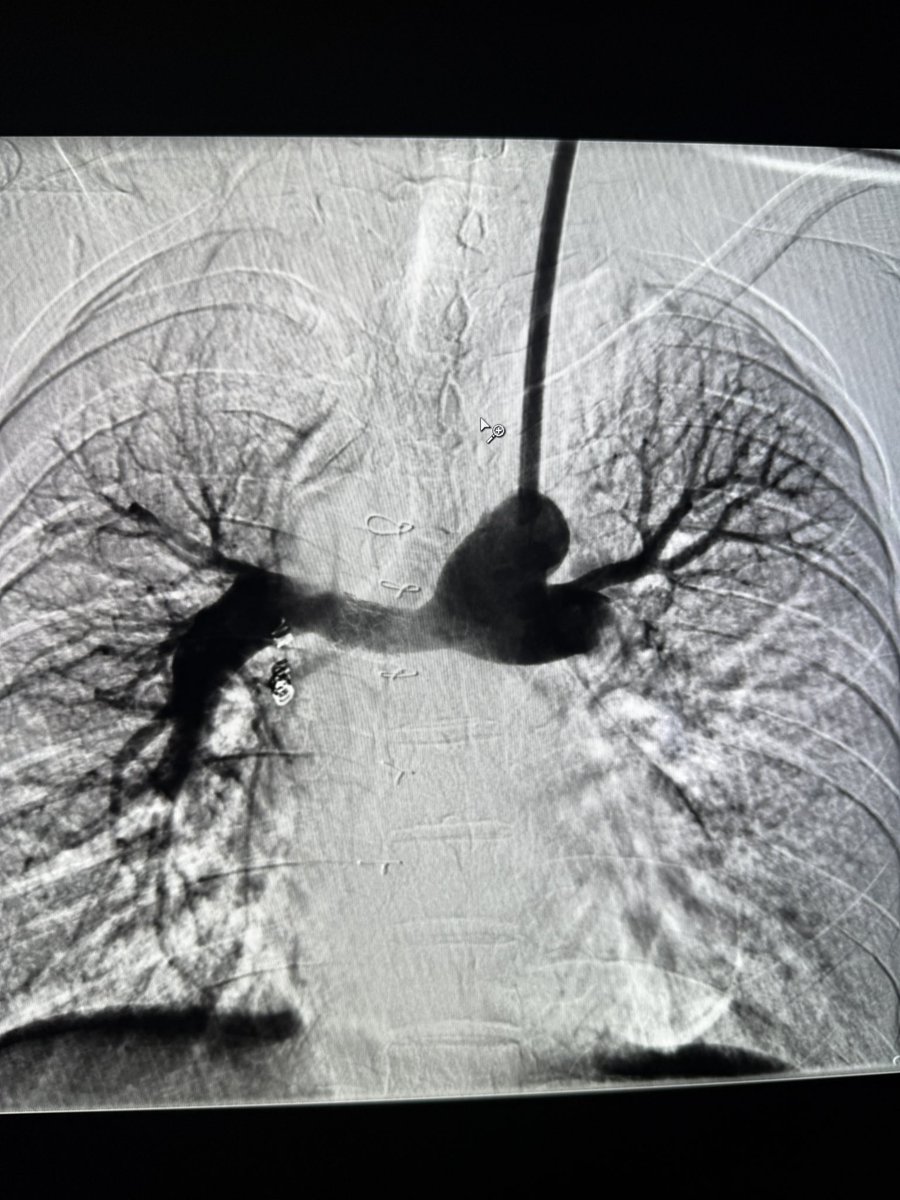

This milestone includes the first 3 TIPS placed in humans at the University of Utah, followed by the 7th and 8th implants in the nation just days later. This achievement represents the next evolution in TIPS technology and reflects Utah-IR’s rise as a leader nationally.

The Utah IR team has successfully implanted five of the first 8 including the First-in-Human 6-10mm Controlled Expansion Viatorr Stent, marking a significant advancement in Transjugular Intrahepatic Portosystemic Shunt (TIPS) procedures.